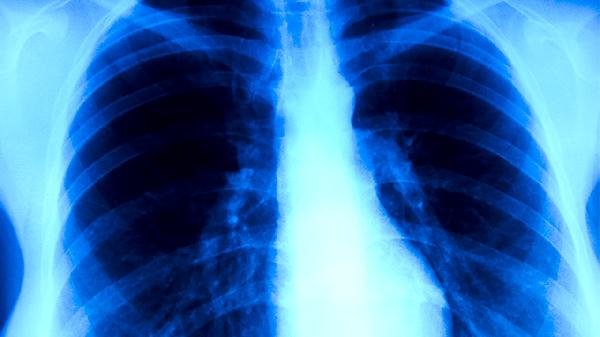

肺结核患者通常需遵医嘱使用异烟肼片、利福平胶囊、吡嗪酰胺片、乙胺丁醇片、链霉素注射液等抗结核药物。肺结核是由结核分枝杆菌感染引起的慢性传染病,需规范使用联合用药方案以杀灭病原体并防止耐药性产生。

肺结核患者应严格遵循早期、联合、适量、规律、全程的用药原则,完成6-9个月的标准疗程。治疗期间保持高蛋白饮食如鸡蛋、鱼肉,适量补充维生素B族和维生素C。注意隔离防护避免传染他人,定期复查胸部影像学和痰菌检查。出现药物不良反应时须及时就医调整方案,不可自行停药或更改剂量。居住环境需保持通风良好,被褥衣物经常晾晒消毒,适当进行呼吸功能锻炼有助于康复。